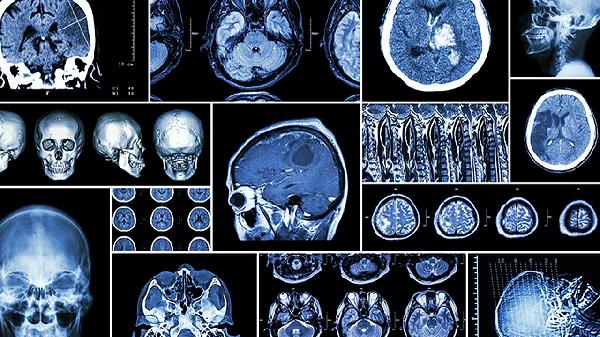

脑血栓饮食注意事项有哪些 介绍脑血栓饮食3技巧

脑血栓患者饮食需注意低盐低脂、均衡营养,主要有控制钠盐摄入、选择优质蛋白、增加膳食纤维三个技巧。